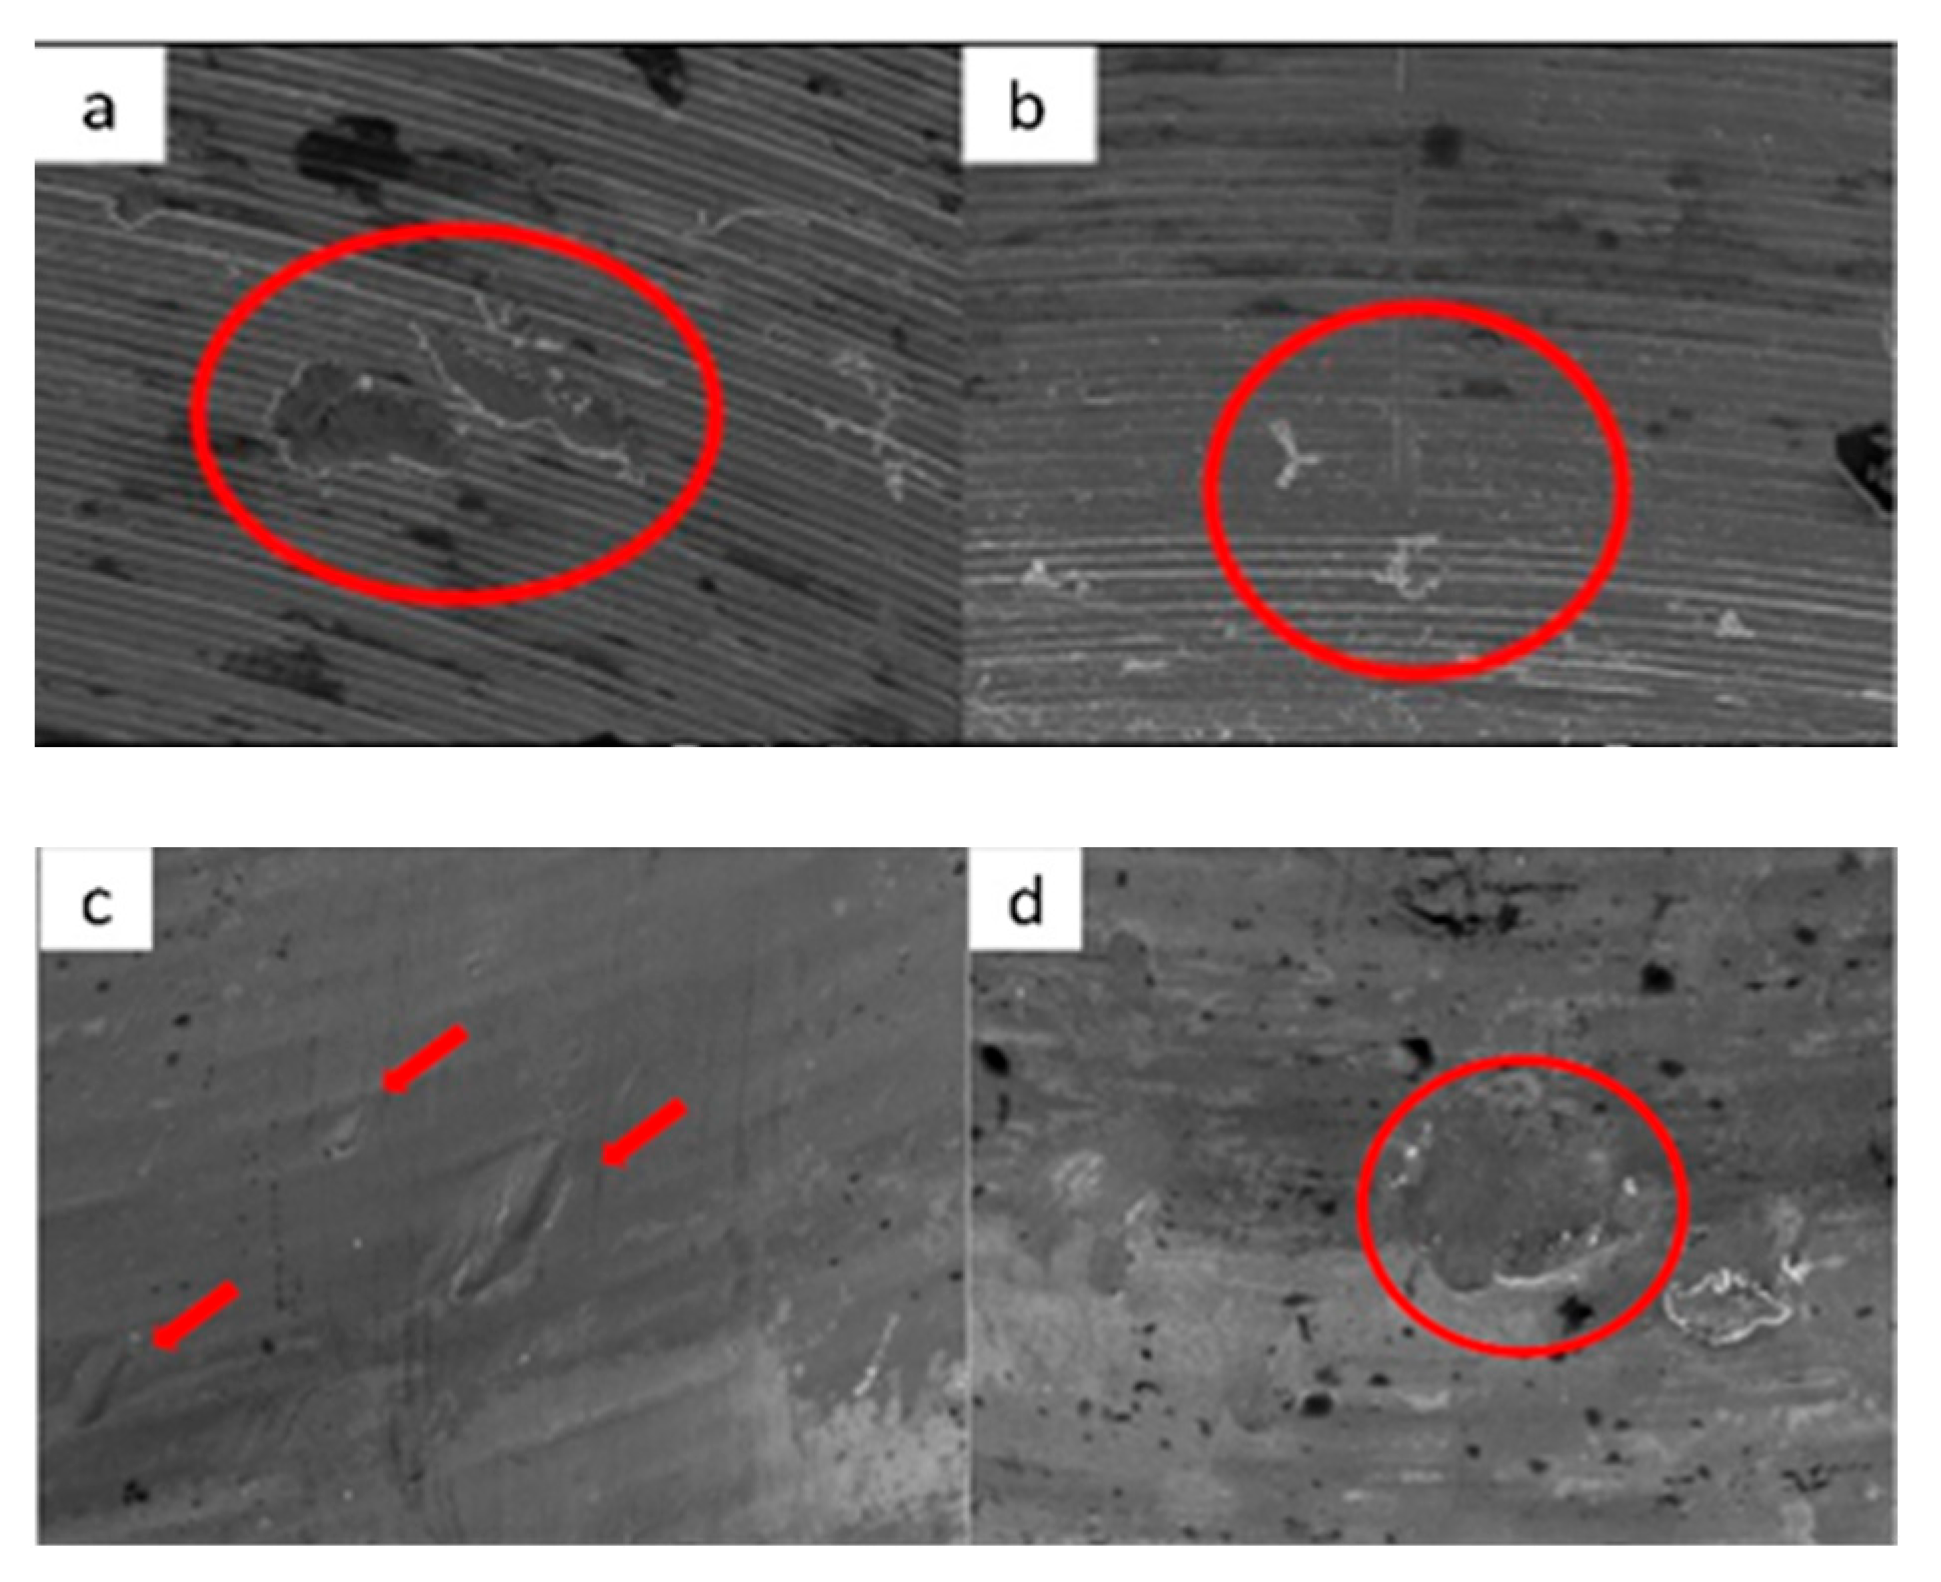

3.1. SEM

3.1.1. KL Implants

3.1.2. Essential Implants

3.1.3. SK2 Implants

3.1.4. Vega Implants

4.1. SEM Evaluation